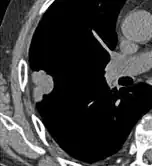

- Pleural retraction is far more common in cancers.[9] It is the pulling of visceral pleura towards the nodule.[9]

Nodule with pleural retraction.[9]

In this case, pleural retraction is seen as a triangular fat component.[9]